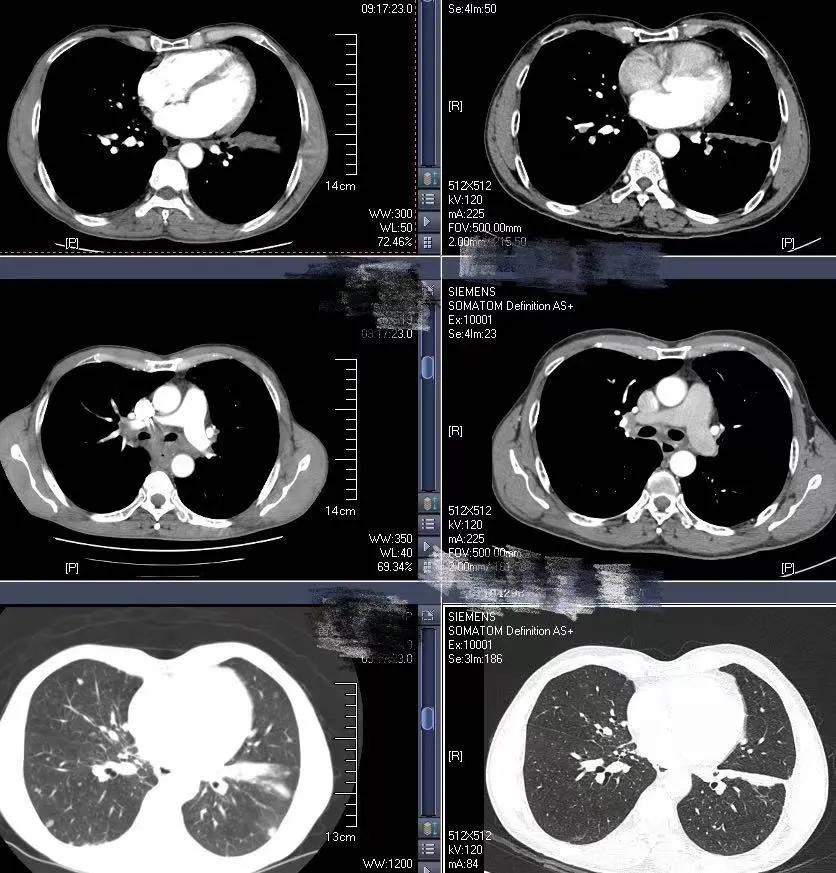

2020-6-19患者行全身PET/CT示:

1、左下肺前内基底段支气管开口处结节,糖代谢增高,考虑中央型肺癌并远端阻塞性炎症、不张;全身(双侧颈部、双侧锁骨上下窝、两侧肺门、纵隔、贲门旁、胰头后方、腹主动脉旁及双侧髂血管旁)多发淋巴结转移;双肺多发转移;肝S4及S5转移;胰头部结节转移;全身多发骨转移;综上,建议活检除外结核。

2、甲状腺双侧叶多发结节,糖代谢增高,不除外恶性肿瘤,建议追踪。左侧肾上腺稍增粗,糖代谢轻度增高,建议追踪。

4、心包少许积液。